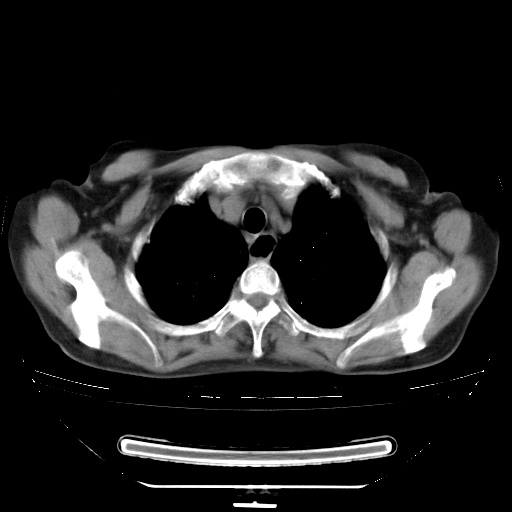

患者女性,72岁,慢性咳嗽3月余,曾抗炎治疗无效果,最近抗结核治疗约半月余,症状缓解。

ct示两肺粟粒状病灶,以两肺上叶尖后段及下叶背段分布为主;首先考虑结核。请战友们分析。